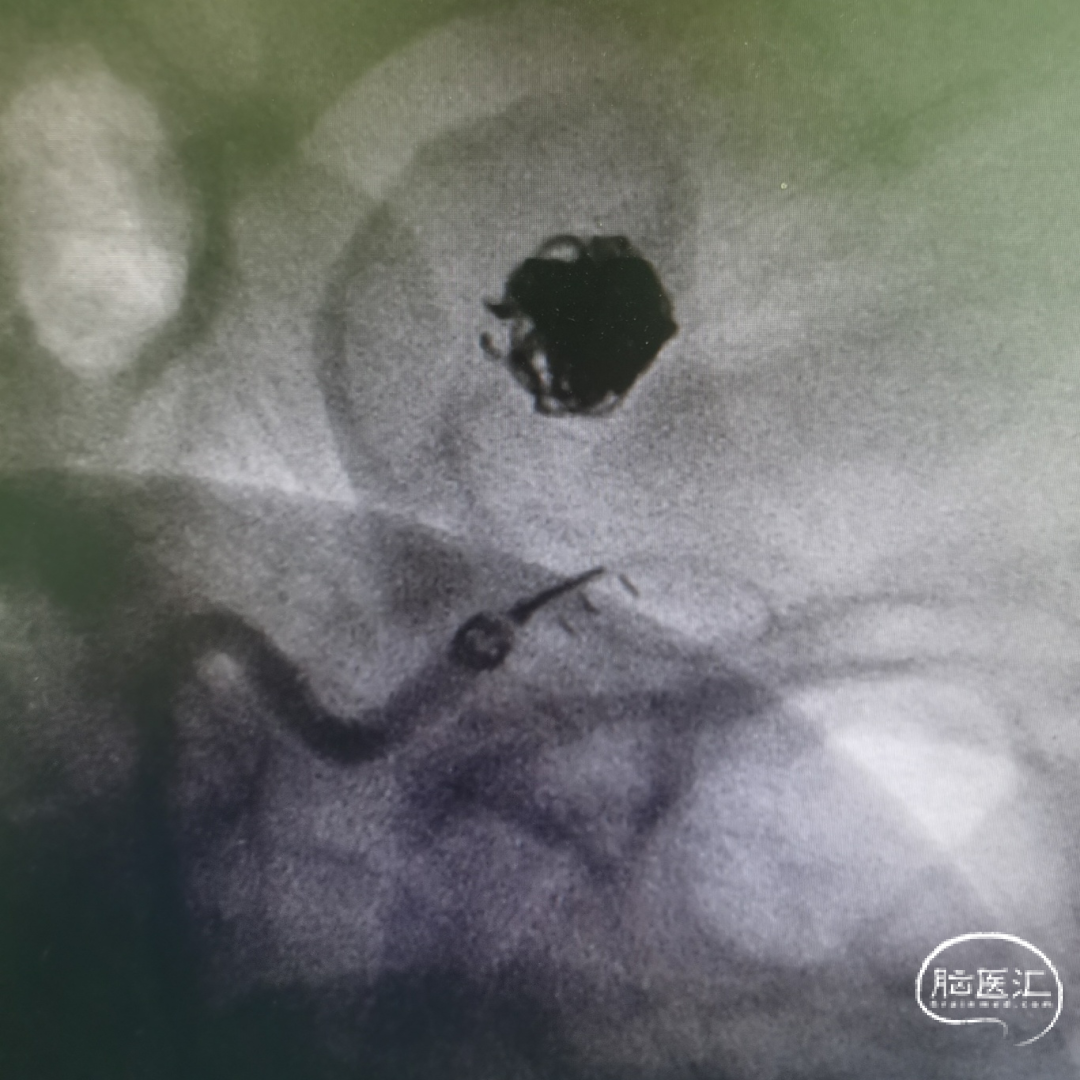

急诊手术(支架+弹簧圈栓塞):

约3.5mm*4.4mm*3.2mm动脉瘤

Atlas+Coil一期栓塞

2周复查造影显示:3*3.2mm颈内末端动脉瘤一期采用Atlas支架辅助弹簧圈栓塞术后2周复发,动脉瘤体增大。

复查3D造影显示:3.5mm*4.4mm*3.2mm颈内末端动脉瘤一期采用Atlas支架辅助弹簧圈栓塞术后2周复发,动脉瘤体增大。